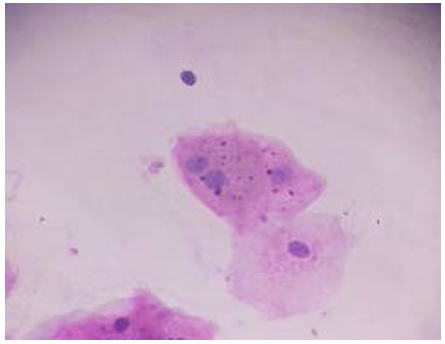

Figure 1: Showing Micronucleus Positivity in Buccal Epithelial cells Stained with Papanicolaou Stain

Figure 2: Showing Micronucleus Positivity in Buccal Epithelial cells Stained with Papanicolaou Stain

Microscopic Examination

Stained slides were examined microscopically using 10×/0.25 and 40×/0.65 objective lenses. Micronuclei were identified as small, round to oval, well-defined cytoplasmic chromatin bodies located adjacent to, but distinct from, the main nucleus, consistent with established diagnostic criteria.